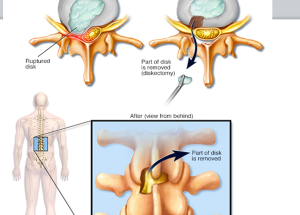

Expert spine services including minimally invasive surgery, pain management, and deformity correction.